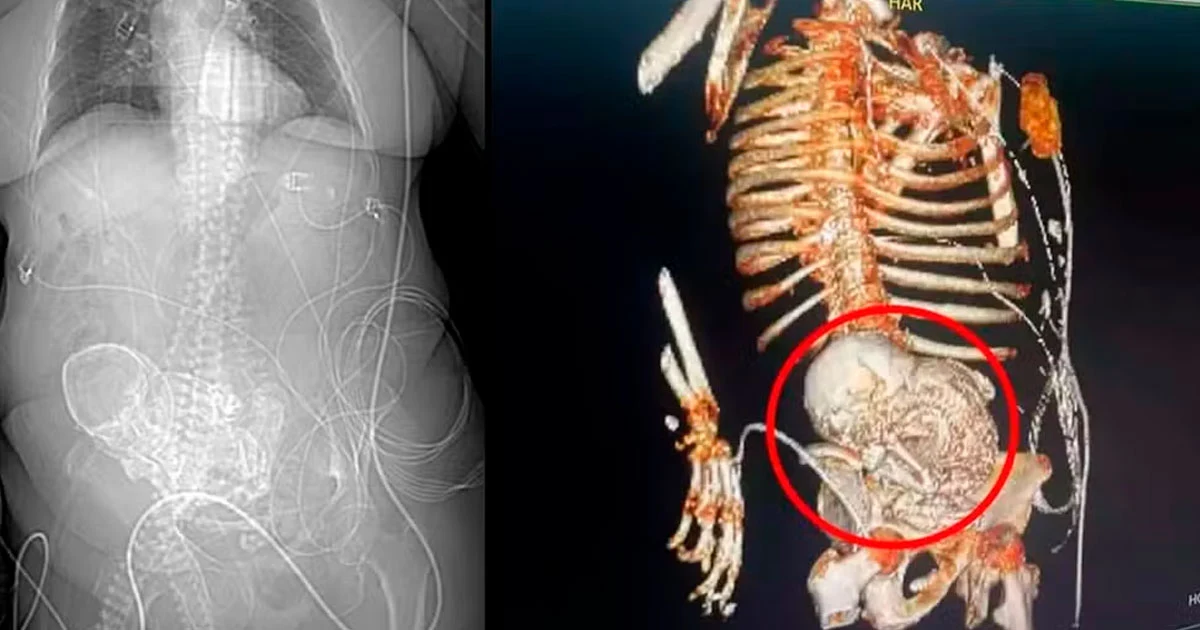

A história de Daniela, que deixou para trás uma família com sete filhos e 40 netos, começou a tomar um rumo inesperado no dia 14 de março, quando dores intensas a levaram ao hospital da região sul do estado. Uma tomografia 3D revelou a presença de um "bebê de pedra" em seu abdômen, um fenômeno conhecido como litopedia, caracterizado pela calcificação de um feto após uma gravidez ectópica não reconhecida. A equipe médica estimou que o feto estava no corpo de Daniela por 56 anos, desde sua última gestação.

Idosa morreu após descobrir bebê calcificado em abdômen. — Foto: Reprodução

O secretário de saúde de Ponta Porã, Patrick Derzi, destacou a raridade do caso, explicando que a litopedia ocorre quando o feto de uma gravidez abdominal morre e se calcifica, podendo permanecer não detectado por décadas e potencialmente causar complicações futuras. Este diagnóstico surpreendente levou à decisão de realizar uma cirurgia de emergência para remover o feto calcificado, um procedimento que, infelizmente, Daniela não sobreviveu. Após a cirurgia, ela foi transferida para a Unidade de Tratamento Intensivo (UTI), onde veio a falecer devido a uma infecção generalizada originada de uma infecção urinária.